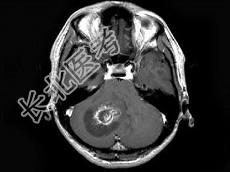

单项选择题男,33岁, 阵发性头痛伴呕吐行走不稳1个月,MRI平扫及增强扫描如图, 最可能的诊断是 ( )

A、右小脑星形细胞瘤

B、右小脑脓肿

C、右小脑血管母细胞瘤

D、转移瘤